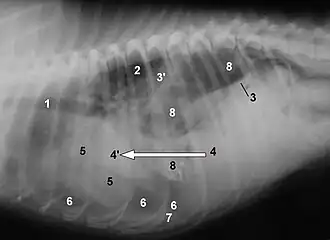

La rotura diafragmática es una complicación común y bien conocida de los traumatismos abdominales contusos en perros y gatos. Los órganos que se hernian en la cavidad pleural vienen determinados por la localización de la rotura. Lo más habitual es que se trate de desgarros circunferenciales que se producen en la unión del diafragma y la costilla. En estos casos, los órganos que se hernian pueden ser el hígado, el intestino delgado, el estómago, el bazo, el epiplón o el útero. Los desgarros dorsales son infrecuentes y pueden provocar la herniación de un riñón hacia el tórax. Los síntomas incluyen dificultad para respirar, vómitos, colapso y ausencia de órganos palpables en el abdomen. Los síntomas pueden empeorar rápidamente y ser letales, sobre todo en caso de hemorragia grave, contusión cardíaca o estrangulamiento del intestino herniado. También es posible que sólo haya signos sutiles y la afección sólo se detecte incidentalmente meses o años después de la lesión durante una exploración médica.[15]